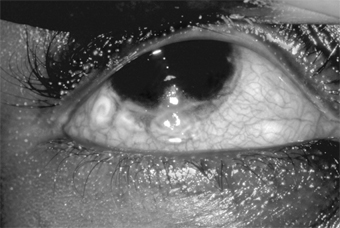

Chapter 5: Conjunctiva IMMUNOLOGIC (ALLERGIC) CONJUNCTIVITIS IMMEDIATE HUMORAL HYPERSENSITIVITY REACTIONS 1. HAY FEVER CONJUNCTIVITIS A mild, nonspecific conjunctival inflammation is commonly associated with hay fever (allergic rhinitis). There is usually a history of allergy to pollens, grasses, animal danders, etc. The patient complains of itching, tearing, and redness of the eyes and often states that the eyes seem to be "sinking into the surrounding tissue." There is mild injection of the palpebral and bulbar conjunctiva, and during acute attacks there is often severe chemosis (which no doubt accounts for the "sinking" description). There may be a small amount of ropy discharge, especially if the patient has been rubbing the eyes. Eosinophils are difficult to find in conjunctival scrapings. A papillary conjunctivitis can occur if the allergen persists (Figure 5-10). Treatment consists of the instillation of local vasoconstrictors during the acute phase (epinephrine, 1:1000 solution applied topically, will relieve the chemosis and symptoms within 30 minutes). Cold compresses are helpful to relieve itching, and antihistamines by mouth are of some value. The immediate response to treatment is satisfactory, but recurrences are common unless the antigen is eliminated. Fortunately, the frequency of the attacks and the severity of the symptoms tend to moderate as the patient ages. 2. VERNAL KERATOCONJUNCTIVITIS This disease, also known as "spring catarrh" and "seasonal conjunctivitis" or "warm weather conjunctivitis," is an uncommon bilateral allergic disease that usually begins in the prepubertal years and lasts for 5-10 years. It occurs much oftener in boys than in girls. The specific allergen or allergens are difficult to identify, but patients with vernal keratoconjunctivitis usually show other manifestations of allergy known to be related to grass pollen sensitivity. The disease is less common in temperate than in warm climates and is almost nonexistent in cold climates. It is almost always more severe during the spring, summer, and fall than in the winter. It is most commonly seen in sub-Saharan Africa and the Middle East. The patient usually complains of extreme itching and a ropy discharge. There is often a family history of allergy (hay fever, eczema, etc) and sometimes in the young patient as well. The conjunctiva has a milky appearance, and there are many fine papillae in the lower tarsal conjunctiva. The upper palpebral conjunctiva often has giant papillae that give a cobblestone appearance (Figure 5-11). Each giant papilla is polygonal, has a flat top, and contains tufts of capillaries. A stringy conjunctival discharge and a fine, fibrinous pseudomembrane (Maxwell-Lyons sign) may be noted, especially on the upper tarsus on exposure to heat. In some cases, especially in persons of black African ancestry, the most prominent lesions are located at the limbus, where gelatinous swellings (papillae) are noted. A pseudogerontoxon (arcus-like haze) is often noted in the cornea adjacent to the limbal papillae. Trantas' dots are whitish dots seen at the limbus in some patients with vernal keratoconjunctivitis during the active phase of the disease. Many eosinophils and free eosinophilic granules are found in Giemsa-stained smears of the conjunctival exudate and in Trantas' dots. Micropannus is often seen in both palpebral and limbal vernal keratoconjunctivitis, but gross pannus is unusual. Conjunctival scarring usually does not occur unless the patient has been treated with cryotherapy, surgical removal of the papillae, irradiation, or other damaging procedure. Superficial corneal ("shield") ulcers (oval and located superiorly) may form and may be followed by mild corneal scarring. A characteristic diffuse epithelial keratitis frequently occurs. None of the corneal lesions respond well to standard treatment. The disease may be associated with keratoconus. Treatment Since vernal keratoconjunctivitis is a self-limited disease, it must be recognized that the medication used to treat the symptoms may provide short-term benefit but long-term harm. Topical and systemic steroids, which relieve the itching, affect the corneal disease only minimally, and their side effects (glaucoma, cataract, and other complications) can be severely damaging. Topical cromolyn is a useful prophylactic agent in moderate to severe cases. Vasoconstrictors, cold compresses, and ice packs are helpful, and sleeping (if possible, also working) in cool, air-conditioned rooms can keep the patient reasonably comfortable. Probably the best remedy of all is to move to a cool, moist climate. Patients able to do so are benefited if not completely cured. The severe symptoms of an extremely photophobic patient who is unable to function can often be relieved by a short course of topical or systemic steroids followed by vasoconstrictors, cold packs, and regular use of histamine-blocking agents as eyedrops. Newer nonsteroidal anti-inflammatory medications, including ketorolac and lodoxamide, may provide significant symptomatic relief. (See discussion in Chapter 3.) As has already been indicated, the prolonged use of steroids must be avoided since it is all too often followed by herpes simplex keratitis, cataract, glaucoma, and fungal and other opportunistic corneal ulcers. Recent clinical studies have shown that topical 2% cyclosporine eye drops are effective in severe unresponsive cases. Supratarsal injection of depot corticosteroids has been demonstrated to be effective for vernal shield ulcers. Desensitization to grass pollens and other antigens has not been rewarding. Staphylococcal blepharitis and conjunctivitis are frequent complications and should be treated. Recurrences are the rule, particularly in the spring and summer; but after a number of recurrences the papillae disappear completely, leaving no scars. 3. ATOPIC KERATOCONJUNCTIVITIS Patients with atopic dermatitis (eczema) often also have atopic keratoconjunctivitis. The symptoms and signs are a burning sensation, mucoid discharge, redness, and photophobia. The lid margins are erythematous, and the conjunctiva has a milky appearance. There are fine papillae, but giant papillae are less developed than in vernal keratoconjunctivitis and occur more frequently on the lower tarsus-unlike the giant papillae of vernal keratoconjunctivitis, which are on the upper tarsus (Figure 5-12). Severe corneal signs appear late in the disease after repeated exacerbations of the conjunctivitis. Superficial peripheral keratitis develops and is followed by vascularization. In severe cases, the entire cornea becomes hazy and vascularized, and visual acuity is reduced. The disease may be associated with keratoconus. There is usually a history of allergy (hay fever, asthma, or eczema) in the patient or the patient's family. Most patients have had atopic dermatitis since infancy. Scarring of the flexure creases of the antecubital folds and of the wrists and knees is common. Like the dermatitis with which it is associated, atopic keratoconjunctivitis has a protracted course and is subject to exacerbations and remissions. Like vernal keratoconjunctivitis, it tends to become less active when the patient reaches the fifth decade. Scrapings of the conjunctiva show eosinophils, though not nearly as many as are seen in vernal keratoconjunctivitis. Scarring of both the conjunctiva and cornea is often seen, and an atopic cataract, a posterior subcapsular plaque, or an anterior shield-like cataract may develop. Keratoconus, retinal detachment, and herpes simplex keratitis are all more than usually frequent in patients with atopic keratoconjunctivitis, and there are many cases of secondary bacterial blepharitis and conjunctivitis, usually staphylococcal. The management of atopic keratoconjunctivitis is often discouraging. Any secondary infection must be treated. Environmental control should be considered. Oral antihistamines including terfenadine (60-120 mg twice daily), astemizole (10 mg four times daily), or hydroxyzine (50 mg at bedtime, increasing to 200 mg at bedtime) have been shown to be of value. Newer nonsteroidal anti-inflammatory medications, including ketorolac and lodoxamide, show promise for symptomatic relief for these patients (see Chapter 3). A short course of topical steroids may relieve symptoms. In severe cases, plasmapheresis may be an adjunct to therapy. In advanced cases with severe corneal complications, corneal transplantation may be needed to improve the visual acuity. 4. GIANT PAPILLARY CONJUNCTIVITIS Giant papillary conjunctivitis with signs and symptoms resembling those of vernal conjunctivitis may develop in patients wearing plastic artificial eyes or contact lenses. It is probably a basophil-rich delayed hypersensitivity disorder (Jones-Mote hypersensitivity), perhaps with an IgE humoral component. Use of glass instead of plastic for prostheses and spectacle lenses instead of contact lenses is curative. If the goal is to maintain contact lens wear, additional therapy will be required. Careful contact lens care, including preservative-free agents, is essential. Hydrogen peroxide disinfection and enzymatic cleaning of contact lenses may also help. Changing to a different brand or style of contact lenses may be necessary if other measures fail. If these treatments are unsuccessful, contact lenses should be discontinued. DELAYED HYPERSENSITIVITY REACTIONS 1. PHLYCTENULOSIS Phlyctenular keratoconjunctivitis is a delayed hypersensitivity response to microbial proteins, including the proteins of the tubercle bacillus, Staphylococcus species, Candida albicans, Coccidioides immitis, Haemophilus aegyptius, and Chlamydia trachomatis serotypes L1, L2, and L3. Until recently, by far the most frequent cause of phlyctenulosis in the USA was delayed hypersensitivity to the protein of the human tubercle bacillus. This is still the commonest cause in regions where tuberculosis is still prevalent. In the USA, however, most cases are now associated with delayed hypersensitivity to S aureus. The conjunctival phlyctenule begins as a small lesion (usually 1-3 mm in diameter) that is hard, red, elevated, and surrounded by a zone of hyperemia. At the limbus it is often triangular in shape, with its apex toward the cornea. In this location it develops a grayish-white center that soon ulcerates and then subsides within 10-12 days. The patient's first phlyctenule and most of the recurrences develop at the limbus, but there may also be corneal, bulbar, and, very rarely, even tarsal phlyctenules. Unlike the conjunctival phlyctenule, which leaves no scar, the corneal phlyctenule develops as an amorphous gray infiltrate and always leaves a scar. Consistent with this difference is the fact that scars form on the corneal side of the limbal lesion and not on the conjunctival side. The result is a triangular scar with its base at the limbus-a valuable sign of old phlyctenulosis when the limbus has been involved. Conjunctival phlyctenules usually produce only irritation and tearing, but corneal and limbal phlyctenules are usually accompanied by intense photophobia (Figure 5-13). Phlyctenulosis is often triggered by active blepharitis, acute bacterial conjunctivitis, and dietary deficiencies. Phlyctenular scarring, which may be minimal or extensive, is often followed by Salzmann's nodular degeneration. Histologically, the phlyctenule is a focal subepithelial and perivascular infiltration of small round cells, followed by a preponderance of polymorphonuclear cells when the overlying epithelium necrotizes and sloughs-a sequence of events characteristic of the delayed tuberculin type hypersensitivity reaction. Phlyctenulosis induced by tuberculoprotein and the proteins of other systemic infections responds dramatically to topical corticosteroids. There is a major reduction of symptoms within 24 hours and disappearance of the lesion in another 24 hours. Phlyctenulosis produced by staphylococcal proteins responds somewhat more slowly. Topical antibiotics should be added for active staphylococcal blepharoconjunctivitis. Treatment should be aimed at the underlying disease, and the steroids, when effective, should be used only to control acute symptoms and persistent corneal scarring. Severe corneal scarring may call for corneal transplantation. 2. MILD CONJUNCTIVITIS SECONDARY TO CONTACT BLEPHARITIS Contact blepharitis caused by atropine, neomycin, broad-spectrum antibiotics, and other topically applied medications is often followed by a mild infiltrative conjunctivitis that produces hyperemia, mild papillary hypertrophy, a mild mucoid discharge, and some irritation (Figure 5-14). Examination of Giemsa-stained scrapings often discloses only a few degenerated epithelial cells, a few polymorphonuclear and mononuclear cells, and no eosinophils. Treatment should be directed toward finding the offending agent and eliminating it. The contact blepharitis may clear rapidly with topical cortico-steroids, but their use should be limited. Long-term use of steroids on the lids may lead to steroid glaucoma and to skin atrophy with disfiguring telangiectasis. PREVIOUS | NEXT Page: 1 | 2 | 3 | 4 | 5 | 6 | 7 | 8 | 9 | 10 | 11 | 12 | 13 | 14 10.1036/1535-8860.ch5 |